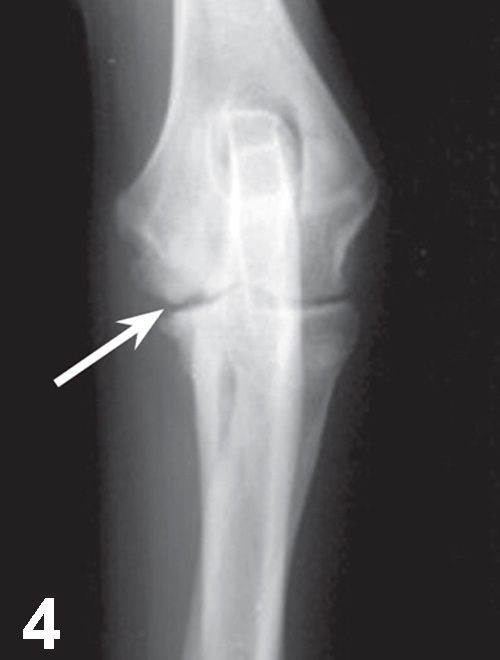

Elbow dysplasia is an umbrella term for several conditions (eg, ununited anconeal process [UAP], medial coronoid disease [MCD], osteochondrosis [OC]/OCD, incongruency) resulting in OA. Most patients are affected by only 1 or 2 of these conditions at the same time (eg, fragmented medial coronoid process, humeral OCD). The causes are multifactorial; genetic and environmental factors are involved. Dogs present with unilateral or bilateral lameness or stiffness of the forelimbs with effusion, pain, and decreased range of motion of the elbow. In dogs older than 5 months of age, radiographs of the joint may show a radiolucent line in the anconeal process (ie, UAP; Figure 3), an articular defect in the medial aspect of the humeral condyle (ie, OC, OCD; Figure 4), sclerosis and blunting of the medial coronoid process (ie, MCD), degenerative changes, or joint incongruency.

Mediolateral radiograph of the elbow in a 7-month-old German shepherd dog with joint effusion and pain of the elbow. A radiolucent line (arrow) can be observed between the anconeal process and proximal ulna, consistent with UAP.